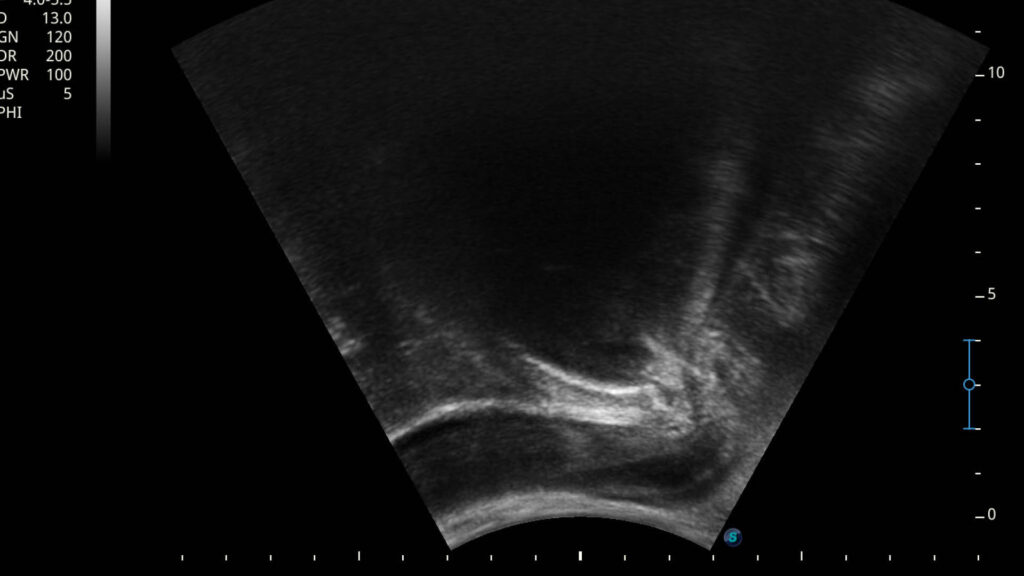

1. Visuelles Feedback in Echtzeit: Wolfgang Brunner-Fruhmann setzt einen Ultraschallkopf auf euren Damm-Bereich. Auf einem Bildschirm seht ihr live, wie sich die Muskulatur bewegt, wenn ihr den Beckenboden anspannt oder entspannt. Außerdem kann man dabei beobachten, wie sich auch die umliegenden Strukturen, wie zum Beispiel die Harnröhre bewegen und die Position verändern. Ein wesentlicher Faktor für die Kontinenz.

2. Präzision und Korrektur: Ihr erhaltet eine sofortige, visuelle Rückmeldung über die Qualität eurer Muskelaktivierung. Ist die Anspannung korrekt? Haltet ihr die Luft an? Spannt ihr zu stark oder zu schwach an? Kompensiert ihr mit anderen Muskeln? Der Therapeut kann euch sofort korrigieren und ihr seht euren Fortschritt auf dem Bildschirm.

3. Schnellerer Lernerfolg: Die visuelle Darstellung fördert das Körpergefühl und die neurologische Ansteuerung der Muskulatur immens. Was vorher abstrakt war, wird sichtbar. Das Gehirn lernt durch dieses klare Feedback deutlich schneller, die wichtigen Muskeln isoliert und effektiv anzusteuern.

4. Motivation und Kontrolle: Ihr seht eure Erfolge schwarz auf weiß bzw. in Graustufen auf dem Bildschirm. Das ist ein riesiger Motivationsfaktor und gibt euch ein Gefühl der Kontrolle über euren Körper zurück.

„Mit dem Echtzeit-Ultraschall nehmen wir unseren Patienten die Unsicherheit. Sie sehen, wie die tiefen Beckenbodenstrukturen arbeiten. Wir überspringen damit oft langwierige Phasen der reinen Wahrnehmungsschulung und kommen schneller zur effektiven Kräftigung“, betont Wolfgang Brunner-Fruhmann.